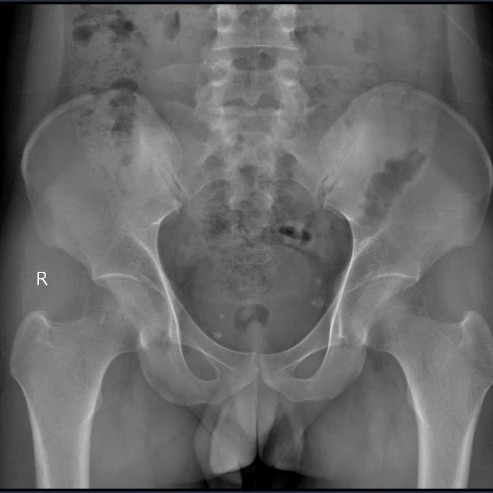

Tại Khoa Khám chữa bệnh theo yêu cầu và quốc tế, Bệnh viện E, ThS.BSNT Nguyễn Mạnh Quyết nhận thấy đây là trường hợp đau cột sống kiểu viêm – dấu hiệu then chốt gợi ý bệnh lý viêm khớp mạn tính. Bệnh nhân được chỉ định chụp X-quang khớp cùng chậu và làm xét nghiệm gen HLA-B27.

Kết quả cho thấy, bệnh nhân bị viêm khớp cùng chậu độ III hai bên, HLA-B27 dương tính, CRP và tốc độ lắng máu tăng. Trong khi đó, X-quang cột sống cổ vẫn chưa có biểu hiện dính khớp hay gai xương.

Kết quả chụp Xquang còn cho thấy bệnh nhân bị viêm khớp cùng chậu độ III hai bên.